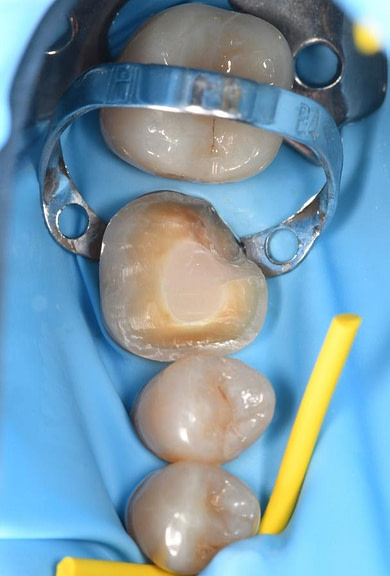

The surgical phase of the implant treatment is a critical step in ensuring the success and longevity of the final restoration.

I utilized 3Shape Implant Studio, a module within the 3shape Unite Platform, to plan and execute the surgical procedure.

Pre-surgical planning began with acquiring high-quality diagnostic data, including TRIOS intraoral scans and CBCT imaging. The data was imported into 3Shape Implant Studio, where I designed a virtual crown for tooth 24 and planned the precise positioning of the implant, considering critical factors such as sinus proximity, adjacent roots, bone density, and the location of the bony defect.

A custom surgical guide was designed and 3D printed, incorporating all the critical information from the virtual planning. The implant surgery was performed under local anesthesia, with the surgical guide firmly in place to ensure accurate implant placement. Bone grafting was performed to address the bony defect and promote optimal healing.

The Osstem OneGuide kit is used with a fully guided osteotomy and implant placement.

Osstem TSIII D4 x H10mm implant on NoMount driver.